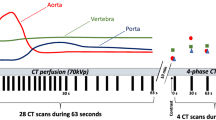

CE scans were performed using iomeprol, a non-ionic iodinated contrast agent for intravenous application (Imeron 400 MCT, Bracco Imaging Deutschland GmbH). Per routine clinical protocol and depending on the clinical situation, a volume of 50 to 70 ml was administered with a flow rate of 3 ml/s. Arterial phases were triggered when the average CT numbers of a volume of interest (VOI) in the descending thoracic aorta exceeded a threshold value of 150 HU. The portal-venous phases started 70 s after contrast administration.

For DLCT-BMD, measurements in native scans averaged to 102.95 ± 46.33 mg/ml (mean ± SD), whereas arterial (112.23 ± 7.88 mg/ml [+ 9.0%]) and portal-venous (126.86 ± 53.89 mg/ml [+ 23.2%]) scan phases revealed substantially higher results (Fig. 2). DLCT-BMD from AR and PV showed high correlations (r = 0.994 [95% confidence interval, 0.991–0.996] and r = 0.989 [0.984–0.992]), yet a low agreement with DLCT-BMD from NE.

Conventionally calculated BMD showed similar, yet continuously lower results: native BMD values were 97.00 ± 43.48 mg/ml, whereas in CE phases, likewise, BMD values were substantially higher with 106.44 ± 44.35 mg/ml (+ 9.7%) for AR and 119.67 ± 42.93 mg/ml (+ 23.3%) for PV, respectively.

Before this conversion, DLCT-BMD values were consistently higher for all scan phases when measured in contrast-enhanced scans compared with their native BMD references (Fig. 2). This represents the challenge of adequately separating intravascular iodine within the vertebra from HA, which is attributable to similar spectral absorption behavior of the two components. Another explanation for this BMD variation is the present dual-layer set-up, which cannot provide absolute selectivity on the detector level due to an overlap of the high- and low-energy spectra [25, 26].